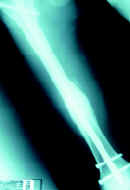

Caso clínico No 4. Paciente de 30 años, con fractura conminuta del fémur derecho; consolidación a las 16 semanas.